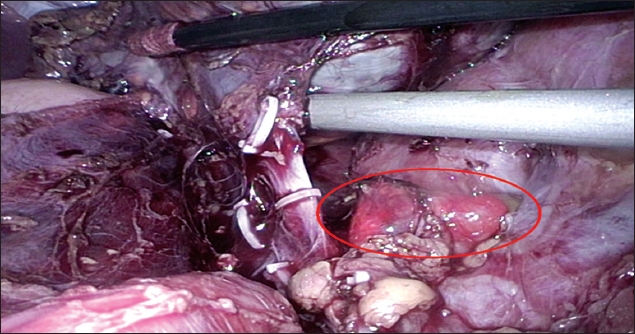

During the resection of the left adrenal gland, a small, pale brown nodule (1.3 cm × 1.2 cm × 0.4 cm in size) was noted over the left renal vein (

Fig. 2

Photograph shows laparoscopic view of the accessory adrenal gland (circled).